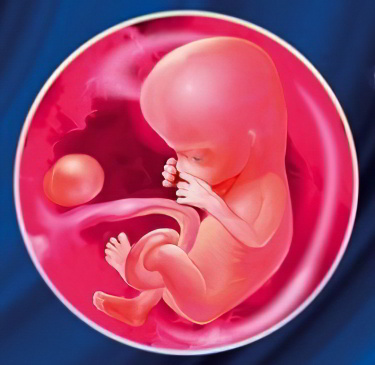

Развитие плода на 13 неделе беременности

На данном этапе беременности ваш малыш активно растёт. Пропорции его тела изменяются: голова, которая раньше казалась большой по сравнению с туловищем, теперь увеличивается медленнее, чем корпус. Вскоре плод приобретёт привычные для нас пропорции маленького ребёнка. Жировая клетчатка пока отсутствует и начнёт формироваться лишь в третьем триместре. Тело малыша покрыто только кожей, сквозь которую видны кровеносные сосуды.

Лицо плода становится более выразительным: выделяются подбородок и нос, а глаза и уши занимают свои места. Развивающаяся нервная система позволяет ребёнку выполнять произвольные движения, гримасничать, зевать и улыбаться. В ротовой полости уже сформировались зачатки всех молочных зубов, активно развивается голосовой аппарат, а также появился сосательный рефлекс.

Параметры плода на 13-й неделе:

- Вес – 15-25 г;

- КТР (копчиково-теменной размер) – 8-9 см.

При наблюдении за активностью малыша можно заметить, что у него есть периоды сна и бодрствования, причём бодрствование становится довольно активным. Движения плода становятся менее хаотичными и более упорядоченными, что связано с развитием костно-мышечной системы.

На 13-й неделе происходит важное событие: половой бугорок начинает дифференцироваться в пенис у мальчиков или клитор у девочек. В зависимости от пола у плода формируются предстательная железа или яичники, которые занимают своё место в малом тазу. На этом этапе у девочек уже имеются зачатки примерно 2 миллионов будущих яйцеклеток, количество которых после рождения уменьшится.